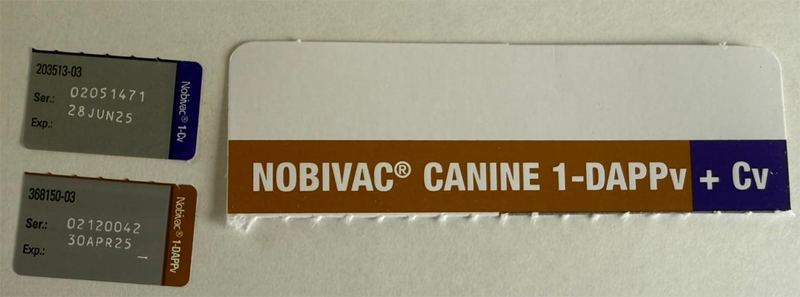

| Insert Date | Name | Dosage | Veccines file | Due Date |

| June 15, 2025 | Virbagen SHAPPi/Nobivac L4 | 1ML |

|

July 15, 2025 |

| May 15, 2025 | Nobivac Canine 1-DAPPv | 1ML |

|

June 15, 2025 |